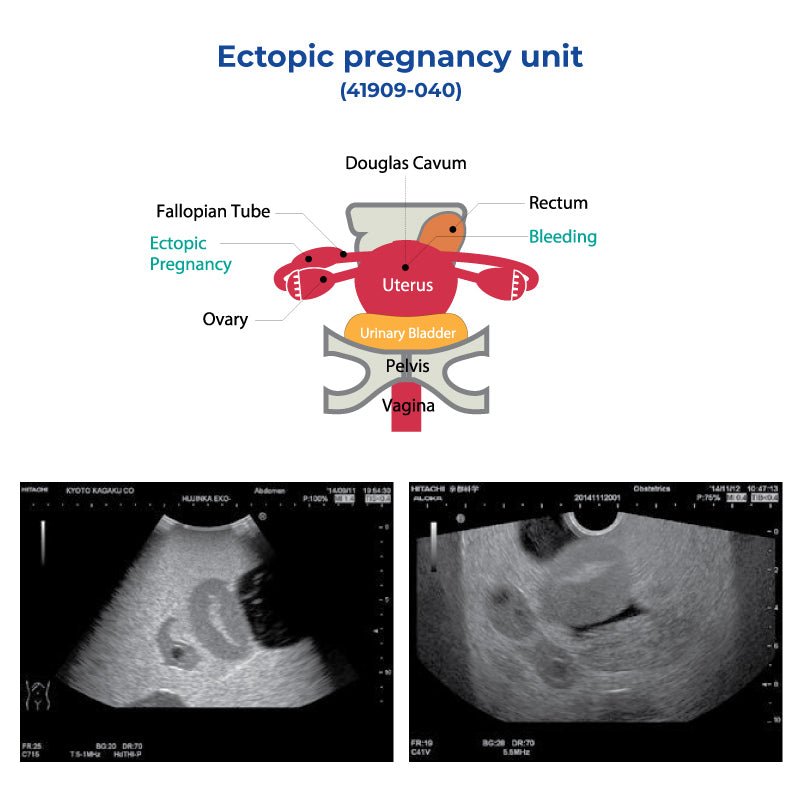

Baby girl born 'pregnant' with twin fetuses | FOX 13 Seattle, Ectopic Pregnancy Unit – GTSimulators.com,

Ectopic Pregnancy Unit – GTSimulators.com, ectopic-pregnancy-unit-kk-,